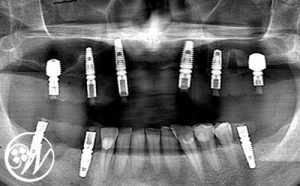

① 上顎:抜歯即時埋入+即日仮歯

上顎は抜歯と同時にインプラントを6本埋入し、当日に固定式の仮歯(スクリュー固定)まで装着しました。

インプラント埋入後